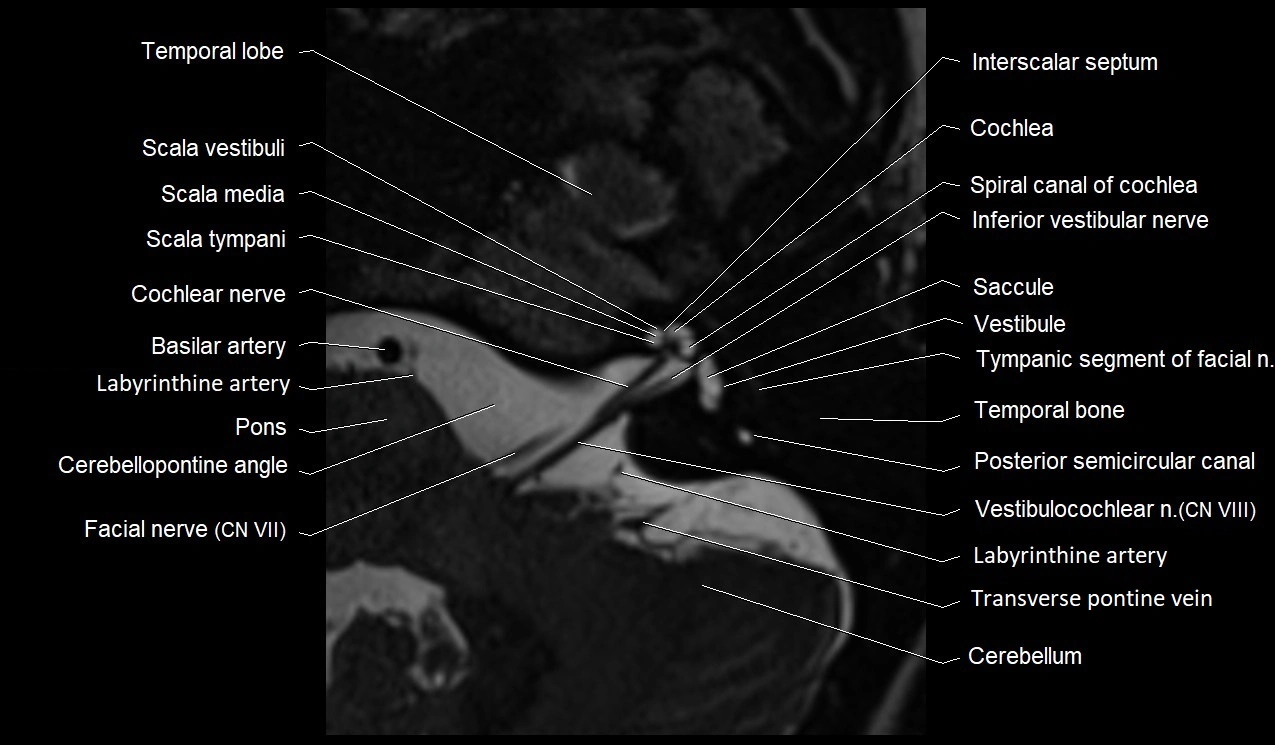

MRI Appearance

• The abducens nerve is a small, thin, linear structure

• Best visualized on high-resolution T2-weighted 3D MRI sequences (e.g., FIESTA or CISS)

• Seen as a hypointense (dark) line running from the brainstem at the pontomedullary junction, traversing the prepontine cistern, and entering Dorello’s canal under the petrosphenoidal ligament, then into the cavernous sinus, and finally the orbit

• May be challenging to visualize in standard MRI due to its small size

• Pathology may be inferred by absence, displacement, or enhancement of the nerve

MRI images

image